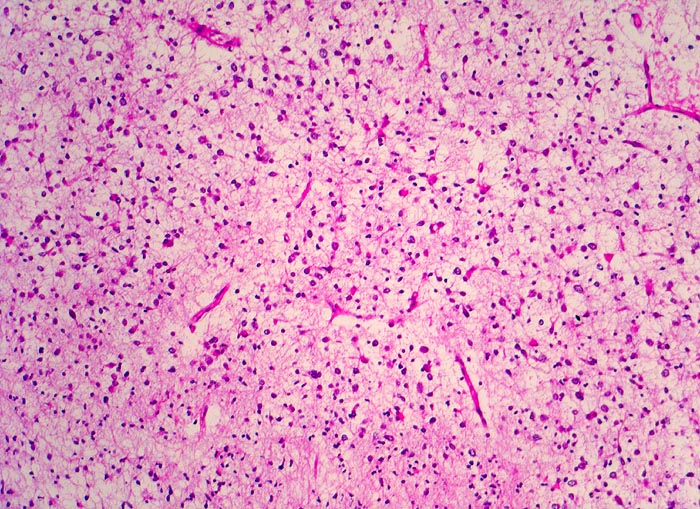

Histologisch bestehen die Oligodendrogliome aus kompakten Aggregaten runder Zellen mit deutlichen Zellgrenzen und klarem Zytoplasmasaum um einen dichten runden zentralen Kern (“Spiegelei”). Die Vakuolisierung des Zytoplasma stellt einen Fixationsartefakt dar und fällt bei Schnellschnitten als diagnostisches Hilfsmittel weg (Gefrierschnitt!). Charakteristisch sind verzweigte Kapillaren. Die Tumorzellen infiltrieren die Hirnrinde diffus und können sich bis in die Meningen ausbreiten.

• Fokale mukoide/zystische Degeneration innerhalb des Tumors mit Ausbildung von Pseudozysten.

• Dichtes Netzwerk verzweigender Kapillaren.

• Tumorzellen umgeben von einem Halo ("Spiegeleier").

• Die Tumorzellen erinnern an Oligodendrozyten der weissen Substanz, haben aber deutlich grössere Kerne.

• Im Gegensatz zum Glioblastoma multiforme monomorphes Zellbild.